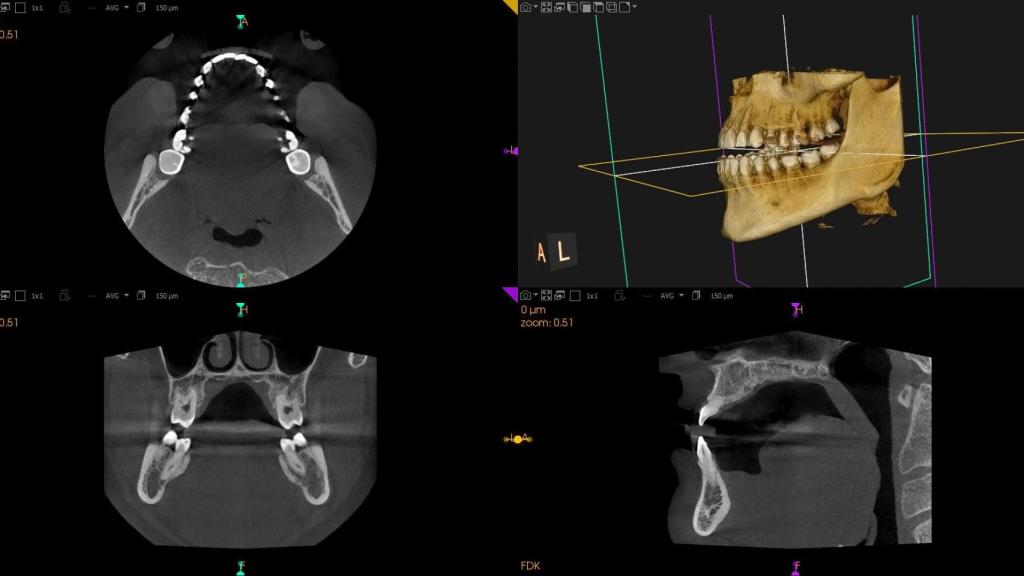

Se trata de una imagen 3D de alta calidad que captura con precisión la dentición completa y terceros molares.

La ortopantomografía es una técnica de Diagnóstico por Imagen mediante la cual se obtiene una imagen tridimensional a partir de la cohesión de varias radiografías bidimensionales. Se trata de una imagen 3D de alta calidad que captura con precisión la dentición completa y terceros molares. La fotografía obtenida de la cavidad bucal es tan exacta que el experto obtiene una recreación rigurosa de las características del paciente. Una ventaja especialmente valorada en una especialidad en la que, en palabras del experto, “los detalles son muy valiosos a la hora de determinar tratamientos de endodoncia, implantología, cirugía oral, ortodoncia y análisis de vías respiratorias”.